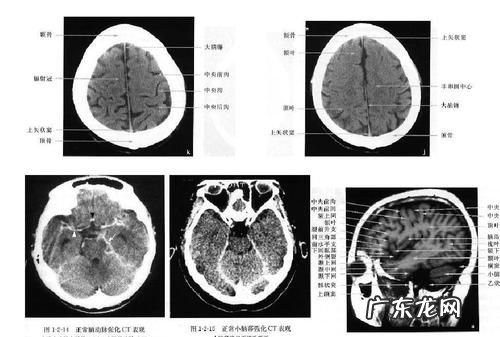

腰椎间盘t1wi等信号,t2wi呈高信号所谓信号就是磁共振片子显示的各个部位的亮度(黑一点或白一点),T1WI是T1加权序列 , T2WI是T2加权序列,这是两个常用的磁共振扫描序列 , 通过电脑设置扫描时身体周围的磁场变化和信号采集模式,可以得到更多诊断信息,T1/T2就是两个常用的 , 不同组织在这些序列检查时信号时不一样的 。所以这句话解读就是:椎间盘在T1加权成像时呈现等、高信号(中等或白的信号) , 在T2加权成像时呈现高信号(白的信号) 。

拍了片子拿到结果看不明白怎么办|内容拓展(来自彩虹神经内科医生)——腔隙性脑梗死

腔隙性脑梗死 , 是脑梗死诸多类型中的一种(如果是微小血栓导致的腔隙性脑梗死,属于脑栓塞的概念),是大的脑动脉分出的的单个小穿通支血管闭塞引起的非皮质性小梗死(梗塞灶的直径一般在0.2-15毫米),这个概念最早来自19世纪,当时医生在尸体解剖中发现这类病灶,发现在大脑的中心部位及脑皮质的下面脑干上有很多的体积很小的缺血性的病灶,后来通过CT、磁共振等技术在活体上也得到了证实 。不过,随着人们这类疾病认识的不断提高 , 腔隙性脑梗死这个诊断名词的争议也越来越大,临床应用也越来越少,它更多的被 “脑小血管病” 等诊断所替代 。